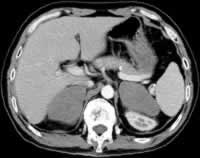

患者,男性,51岁。因反复上腹不适8年,发现双侧肾上腺占位性病变24天,于2003年10月入院。

患者于8年前无明显诱因出现上腹部不适,饱胀、嗳气,在当地医院做胃镜示“慢性浅表性胃炎”,对症治疗2~3个月后症状缓解而自行停止治疗;此后偶有上腹部不适,但皆未在意。入院前24天病人又出现上腹部饱胀不适,且较以往加重,在当地医院做腹部CT示“双侧肾上腺占位,转移瘤可能”。生化检查癌胚抗原(CEA)、甲胎蛋白(AFP)、肝功能等指标均正常。为进一步明确诊断而转入我院。追问病史,病人自发病以来无头晕、头痛,无血压升高、面色苍白、大汗淋漓、心悸等,无软瘫及肢体乏力,无呕吐腹泻,无体重减轻。患者平素体健,已戒烟酒8年。其父因肺癌去世。

实验室检查 血尿粪常规正常,肝肾功能和血脂、血电解质及24h尿电解质均正常。网织红细胞计数1.3%(正常值0.5%~1.5%,下同),血沉12.0 mm/h(0~15 mm/h);乳酸脱氢酶746 IU/L(91~192 IU/L); 血β2-微球蛋白(MG)3.4 ng/ml(1.4~3.4 ng/ml),尿β2-MG 160 ng/ml (<150 ng/ml);糖类抗原CA125、CA199正常;CEA、AFP、甲状腺功能均正常;血浆肾素活性(PRA)、血管紧张素II、血醛固酮、24h尿醛固酮、尿肾上腺素、去甲肾上腺素、多巴胺均正常;血皮质醇(F)8 am 16.3 μg/dl,4 pm 4.8 μg/dl,12 pm 5.7 μg/dl;二次尿F分别是:48 μg /24h和62 μg /24h(20~90μg /24h);二次血促肾上腺皮质激素(ACTH)均正常 ......